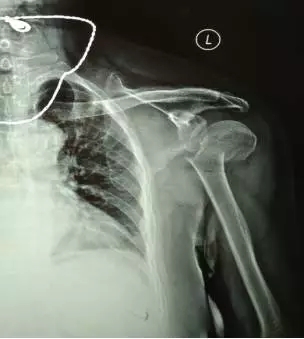

70多歲的鮑阿婆在家人陪同下來(lái)到上海大團(tuán)醫(yī)院就診。大團(tuán)醫(yī)院的醫(yī)生給鮑阿婆左肩部做了X線片檢查。片子拍出來(lái)竟然是左肱骨近端粉碎性骨折。外科頸,大結(jié)節(jié)都碎了,而且骨折端移位很?chē)?yán)重。

正骨科的虞杰主任、邵鵬及葉華磊醫(yī)生看到鮑阿婆的片子也是一皺眉頭,這么厲害的骨折,還真是少見(jiàn),而且移位這么嚴(yán)重,手法復(fù)位的難度也是相當(dāng)大的。不過(guò)患者的信任給了他們很大的動(dòng)力,即使困難也要盡力幫患者。

整復(fù)后復(fù)查X線片,骨折端位置良好。

整復(fù)前